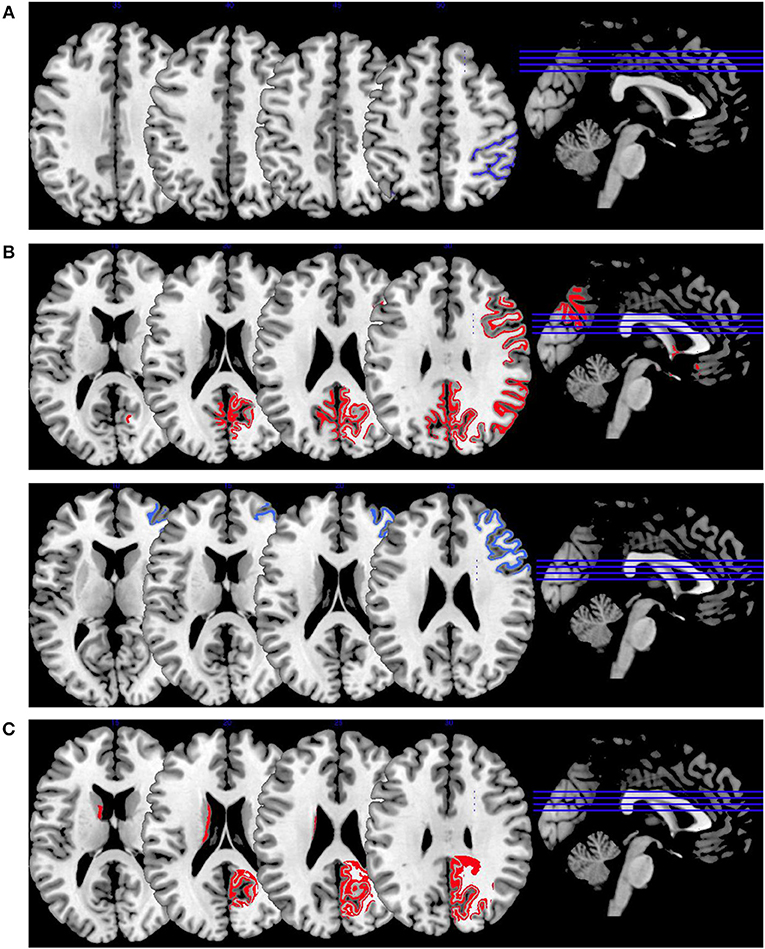

Synthesis of Findings From Studies Using Working Memory Paradigms

In Figure 2, we provide an overview on working memory activation patterns over all reviewed studies. As shown in Figure 2A, violent as opposed to non-violent persons with schizophrenia showed hypoactivation in the right inferior parietal lobe. This is an area known for being part of the working memory network, but it has until now not been observed in specific aggression paradigms. The hypoactivation seen in this group comparison may therefore not be specific for aggression, but may represent working memory dysfunction in the VS group.

Figure 2. Working memory activations. Overview of the working memory brain activation patterns reported by the reviewed studies. Hyperactivations are shown in red, hypoactivations in blue. (A) shows the activation patterns in the group comparison VS vs. NVS with VS<NVS in blue (shown slice numbers are 210, 220, 230, 240) in the contrast 2-back vs. 0-back, (B) shows the activation patterns in the group comparison VS vs. HC with VS>HC in red (shown slice numbers are 170, 180, 190, 200) in the contrasts 1- and 2-back vs. 0-back and cognitive (go/no-go task) vs. reference condition and VS<HC in blue (shown slice numbers are 160, 170, 180, 190) in the contrast NoGo20 vs. NoGo40 and NoGo40 vs. Go and cognitive (go/no-go task) vs. reference condition, (C) shows the activation patterns in the group comparison NVS vs. HC with NVS>HC in red (shown slice numbers are 170, 180, 190, 200) in the contrast 1- and 2-back vs. 0-back.

Figure 2B shows hyperactivations of VS as compared to HC mainly in the frontal lobe and in the middle temporal gyrus. In addition, we see hypoactivations of VS as opposed to HC in the right middle frontal gyrus, the cingulate gyrus, and in the superior temporal gyrus. As frontal regions are typically involved in working memory tasks, this finding is in line with the literature.

In Figure 2C, we present the activation patterns of NVS as compared to HC. NVS hyperactivate the left caudate nucleus and precuneus. The precuneus is known to be involved in working memory processes, while the caudate nucleus usually is not. Still, the latter—as a feedback processor—might be under higher workload conditions while solving these tasks in persons with schizophrenia than in healthy controls. Also, this could be an indicator toward the hypothesis that schizophrenia patients solve working memory tasks differently, namely trying to use information from past experiences to influence their decisions in the tasks.